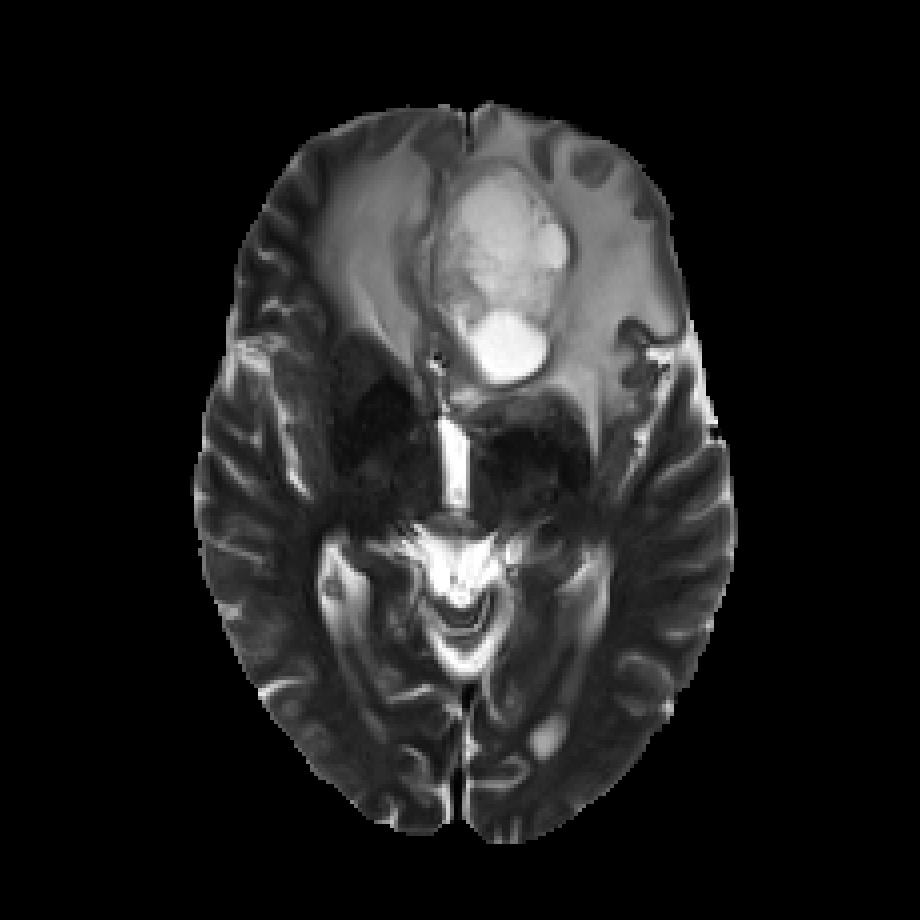

Multimodal medical image segmentation approaches are commonly designed with an end-to-end scheme to learn intermodal associations (Isensee et al., 2018; Zhang et al., 2021a, b; Zhou et al., 2020a, 2022; Ding et al., 2021; Dolz et al., 2018). Certain medical conditions (Figure 2) require segmentor to simultaneously identify multiple regions, such as the tumors, edemas, and necrotic tumor cores. We then refer to the end-to-end learning scheme above as joint learning, as it jointly maps multimodal inputs to single or multiple regions. The joint learning method typically involves fusing multimodal image encoding into a deep encoder-decoder architecture, which outputs the segmentation(s). These methods can be broadly classified into early fusion and mid-term fusion. The former directly concatenates multimodal images as input to the network (Oktay et al., 2018; Isensee et al., 2018; Zhang et al., 2021b; Hatamizadeh et al., 2022; Mai et al., 2022). While the latter uses modality-specific encoders to extract individual features that are later combined in the middle layers of the network and share the same decoder (Xing et al., 2022; Zhang et al., 2021a; Ding et al., 2021; Zhou et al., 2020a, 2022; Dolz et al., 2018).

Furthermore, experienced radiologists often analyze multimodal data in clinical practice by designating a primary modality and several auxiliary modalities for pathological diagnosis. This approach is exemplified in the BraTS challenge (Menze et al., 2014) (Figure 2). In this challenge, the segmentation target was the different areas of glioblastoma, which is the most common type of brain malignancy. Glioblastoma is characterized by its resistance to treatment and poor prognosis, making it a critical focus for advancements in medical imaging and treatment strategies(Li et al., 2019). Human annotators primarily employ the T2 modality222T1, T1CE, T2, and FLAIR represent four modalities generated by MRI imaging technology. for segmenting the edema region while using the FLAIR modality to verify the presence of edema and other fluid-filled structures. Subsequently, the tumor core (TC) is identified through the combined use of T1CE and T1 modalities. The expertise of these radiologists suggests that specific mapping relationships exist between modalities and target areas. Certain modalities facilitate the identification of particular area boundaries, while others serve as supplementary aids. Gleaning insights from this expert knowledge and incorporating it as an inductive bias can potentially reduce the complexity of learning relationships between modalities and corresponding regions. A similar example of adding priors to reduce learning difficulty is DetexNet (Liu et al., 2020), which simplifies low-level representation patterns by embedding expert knowledge.